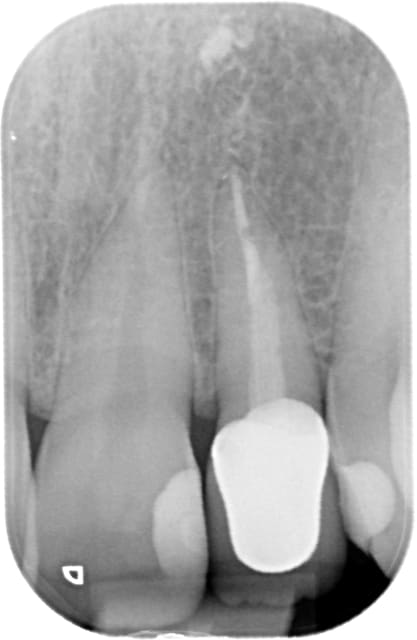

Oui, voici les radios

Pour la 4 (22) au tout début j'avais fait une ccc, mais le collet malgré une chape opaque était grisé, on a donc refait une ccm!